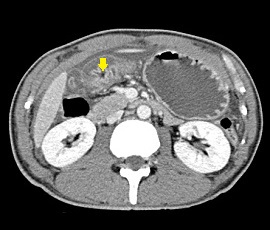

[十二指腸潰瘍穿孔] 手術:腹腔鏡下胃・十二指腸潰瘍穿孔縫合術

CT画像